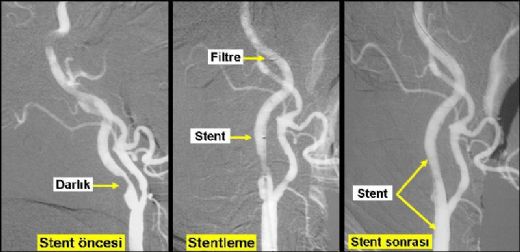

• Cerrahi müdahale: Bazı durumlarda, kanamanın kaynağını ortadan kaldırmak için cerrahi müdahale gerekebilir. Anevrizma veya kan pıhtılarının cerrahi olarak çıkarılması gibi işlemler uygulanabilir.